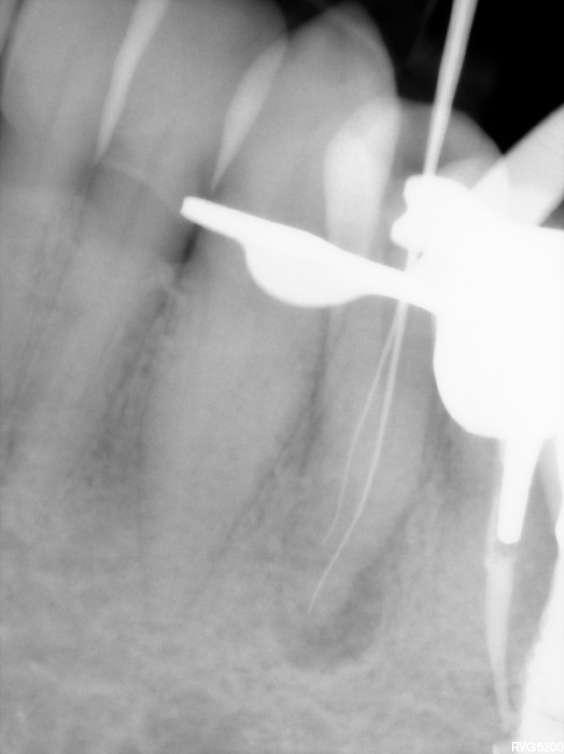

Wenn man sich dieses präoperative Röntgenbild ansieht, sind zwei Hinweise zu diesem endodontischen Fall zu erkennen (Abb. 1): Obliteration der Pulpakammer und enge Kanäle Ungewöhnliche Anatomie der distalen Wurzel

Mit hochtourigen Diamantbohrern wurde eine konventionelle Zugangskavität angelegt und die drei Öffnungen wurden mit Ultraschallspitzen lokalisiert. Die KFeile #08 wurde verwendet, um das endodontische System aller Wurzeln zu erkunden, wobei aber der Apex im distalen Kanal nicht erreicht werden konnte. Das Aufweiten und die Instrumentierung im mittleren Drittel erfolgten mit einer reziprok arbeitenden kleinen (gelben) EdgeOne-Feile (Edge Endo, Albuquerque, NM), die mit Einwärts-Auswärts-Bewegungen von 1-2 mm im Wechsel mit bürstenden Bewegungen zum koronalen Erweitern der Kanäle verwendet wurde. Es wurde eine regelmäßige und reichliche manuelle Spülung mit Lösungen von 5% Natriumhypochlorit durchgeführt. Nach der Aufbereitung des koronalen und mittleren Teils wurde die Arbeitslänge mit der K-Feile #10 bestimmt und das Aufbereitungsverfahren mit martensitischen X7-Instrumenten (Edge Endo, Albuquerque, NM) in den Größen 17 und 25, Konizität .04 abgeschlossen. Die Instrumente wurden mit reziproker Rotation im Uhrzeigersinn (150°-30°) verwendet, um die Torsions- und Biegebelastung zu verringern (Abb. 2).

FALLBERICHT: Abb.1 Abb.2